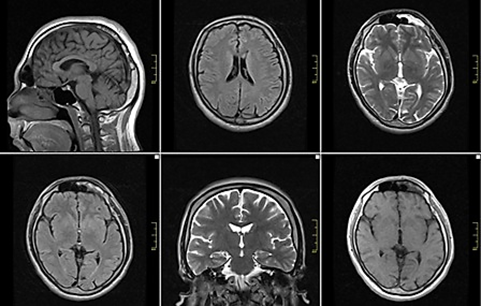

Imaging human soft tissues (organs with high water content) by energy diffusion method is called magnetic imaging. This magnetic imaging is performed by the MRI device with magnets in the device.

During MRI, the powerful scanning magnets in the device align the protons in the same direction, just as the magnet changes the direction of the compass needle. During the shoot, short radio waves are sent to the body at intervals and the protons are out of alignment. When the radio waves are turned off, the protons realign. The movements of the protons during shooting send out radio signals that are detected by the computer.

Protons move at different speeds in different tissues and produce different signals. With the help of a computer, different signals from different tissues are combined on the computer to create a detailed image.

MRI does not contain ionized radiation, so it is safer than other imaging methods. Image creation and creatures in magnets in MRI are achieved by magnetic fields, so they should be used with caution in areas with high metal alloy implants.

MRI is used in all diseases and injuries of the musculoskeletal system, in the diagnosis of cardiovascular diseases, in the detection of all joint problems in the musculoskeletal system, in the diagnosis and treatment planning of ligament and muscle injuries due to sports injuries, in the detection of problems such as tumors, hidden fractures, and osteoporosis, repaired after surgery. It is used for many situations such as monitoring and evaluation of tissues. Again, the diagnosis can be made by applying this method for images such as dementia, nervous system problems, and imaging, which can be encountered especially at an advanced age in the configurations made with the brain.